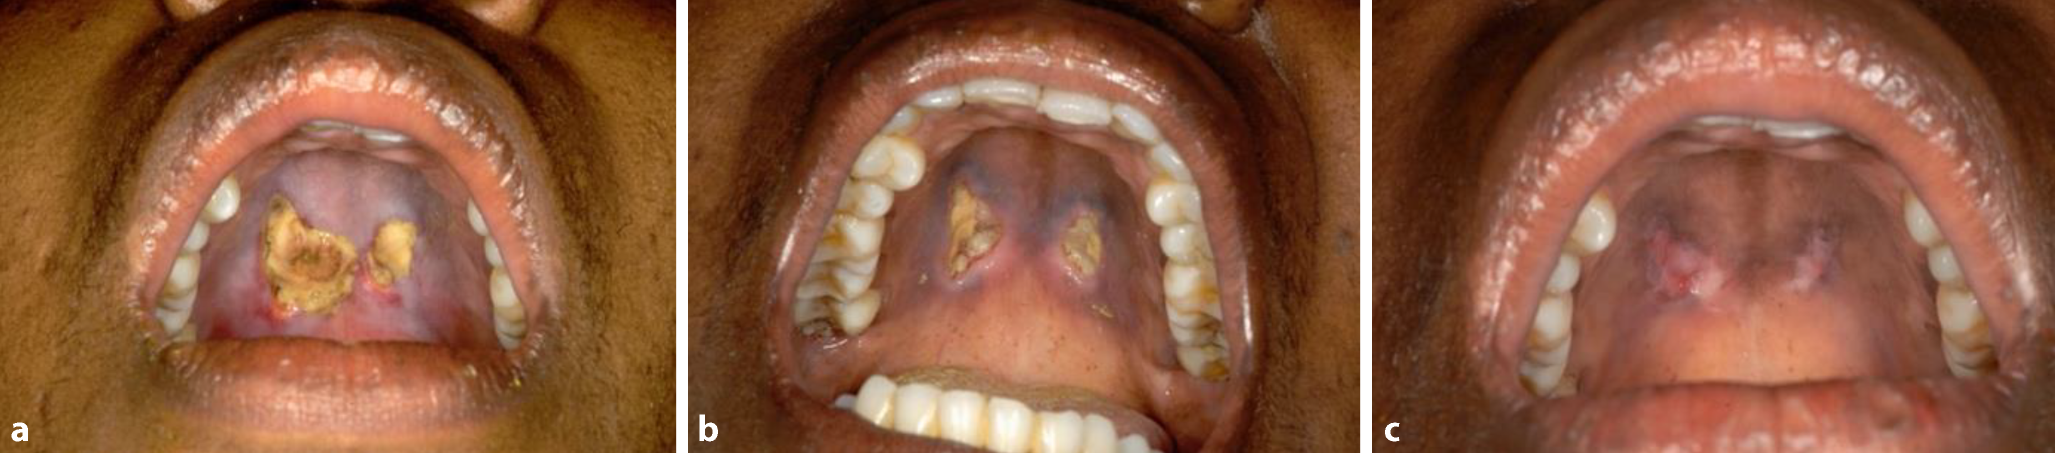

• Tiefe Ulzerationen in der Haut oder Mundschleimhaut können bei Patienten mit AIDS oder anderen schweren Immundefizienzen auftreten und sind oft ein Anzeichen einer umfassenderen CMV-Beteiligung der inneren Organe (Abb. 4).

Abb. 4

ac Beispiel für ein CMV-Ulkus bei einem AIDS-Patienten. Nach Beginn der antiretroviralen Therapie heilten die Läsionen im Verlauf von 2 Monaten ab